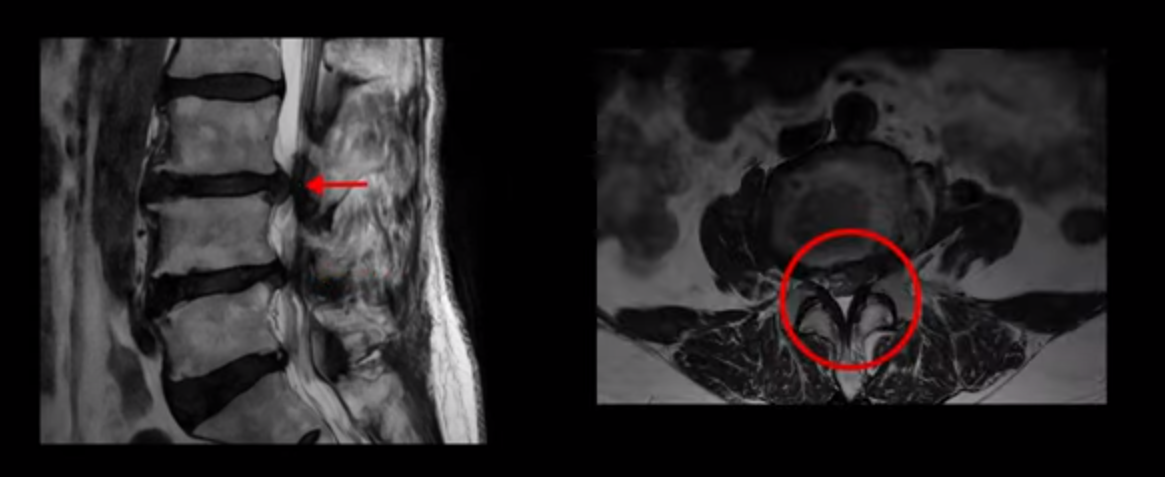

이분은 허리부터 다리, 복숭아뼈까지 극심하게 저리고 아픈 분입니다. MRI를 보시면 허리 4마디가 안 좋습니다.

그중에서도 3번 4번과 4번 5번 마디가 가장 안 좋습니다. 보시다시피 두 마디에 심한 중심성 협착이 있습니다.

이렇게 허리에서 신경이 눌리니까 다리가 저리고 종아리가 터질 듯이 아픕니다. 그래서 걷지를 못하고 가다 쉬고 가다 쉬고 그런 겁니다. 그런데 이런 분들이 수술 없이 치료가 가능한 이유는 근육재활치료와 운동으로 근육이 좋아지면 허리를 더 잘 지탱해 주니까 신경이 덜 눌리게 되는 겁니다. 모든 협착증 환자는 신경 구멍도 좁아져 있지만 근육도 다 망가져 있습니다.